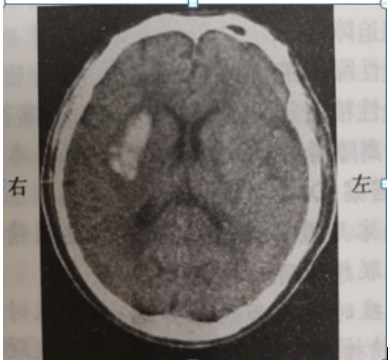

【摸底测试题】男,52岁。清晨锻炼时觉头痛,左侧肢体麻木和无力。有高血压史。半天后到急诊。查体:嗜睡,左侧肢体肌力3级,腱反射活跃,左侧Babinski征阳性。脑CT检查结果见图。可能诊断为?

脑CT

【正确答案】B

【答案解析】

A选项、B选项、C选项、D选项——病例为急性起病的脑血管疾病患者。脑血管病分为缺血性卒中和出血性卒中。脑血栓形成、短暂脑缺血发作、脑栓塞均为缺血性卒中范畴(A选项、C选项、D选项)。脑出血为出血性卒中。根据脑出血性卒中和脑缺血性卒中的鉴别诊断,可以得出选项B为正确答案,故选B。

E选项——脑转移性肿瘤起病较缓,而且CT示病灶周围有大片水肿,为干扰选项,故不选。